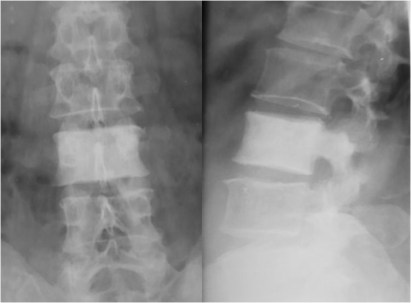

SIGNO DEL BORDE

Engrosamiento de la línea ileopectínea vista en la radiografía de pelvis, que corresponde a la afectación de este hueso en la enfermedad de Paget. Este signo, que corresponde a reacción osteoblástica en la zona, está presente en la mayoría de pacientes con enfermedad de Paget pélvica.